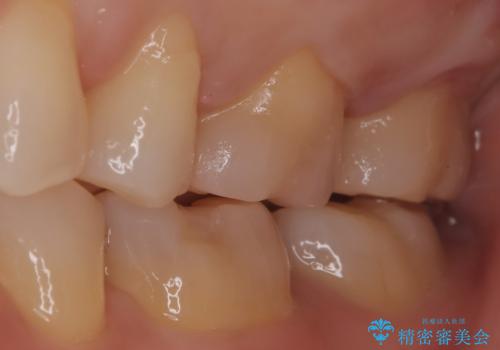

【メタルフリー】セラミックインレーの修復

- メタルフリーを希望された患者さんです。

金属を除去し虫歯の処置をしたあとセラミックインレーにて修復しました。

当院でのセラミックインレーは、ラバーダムを装着してセットしています。